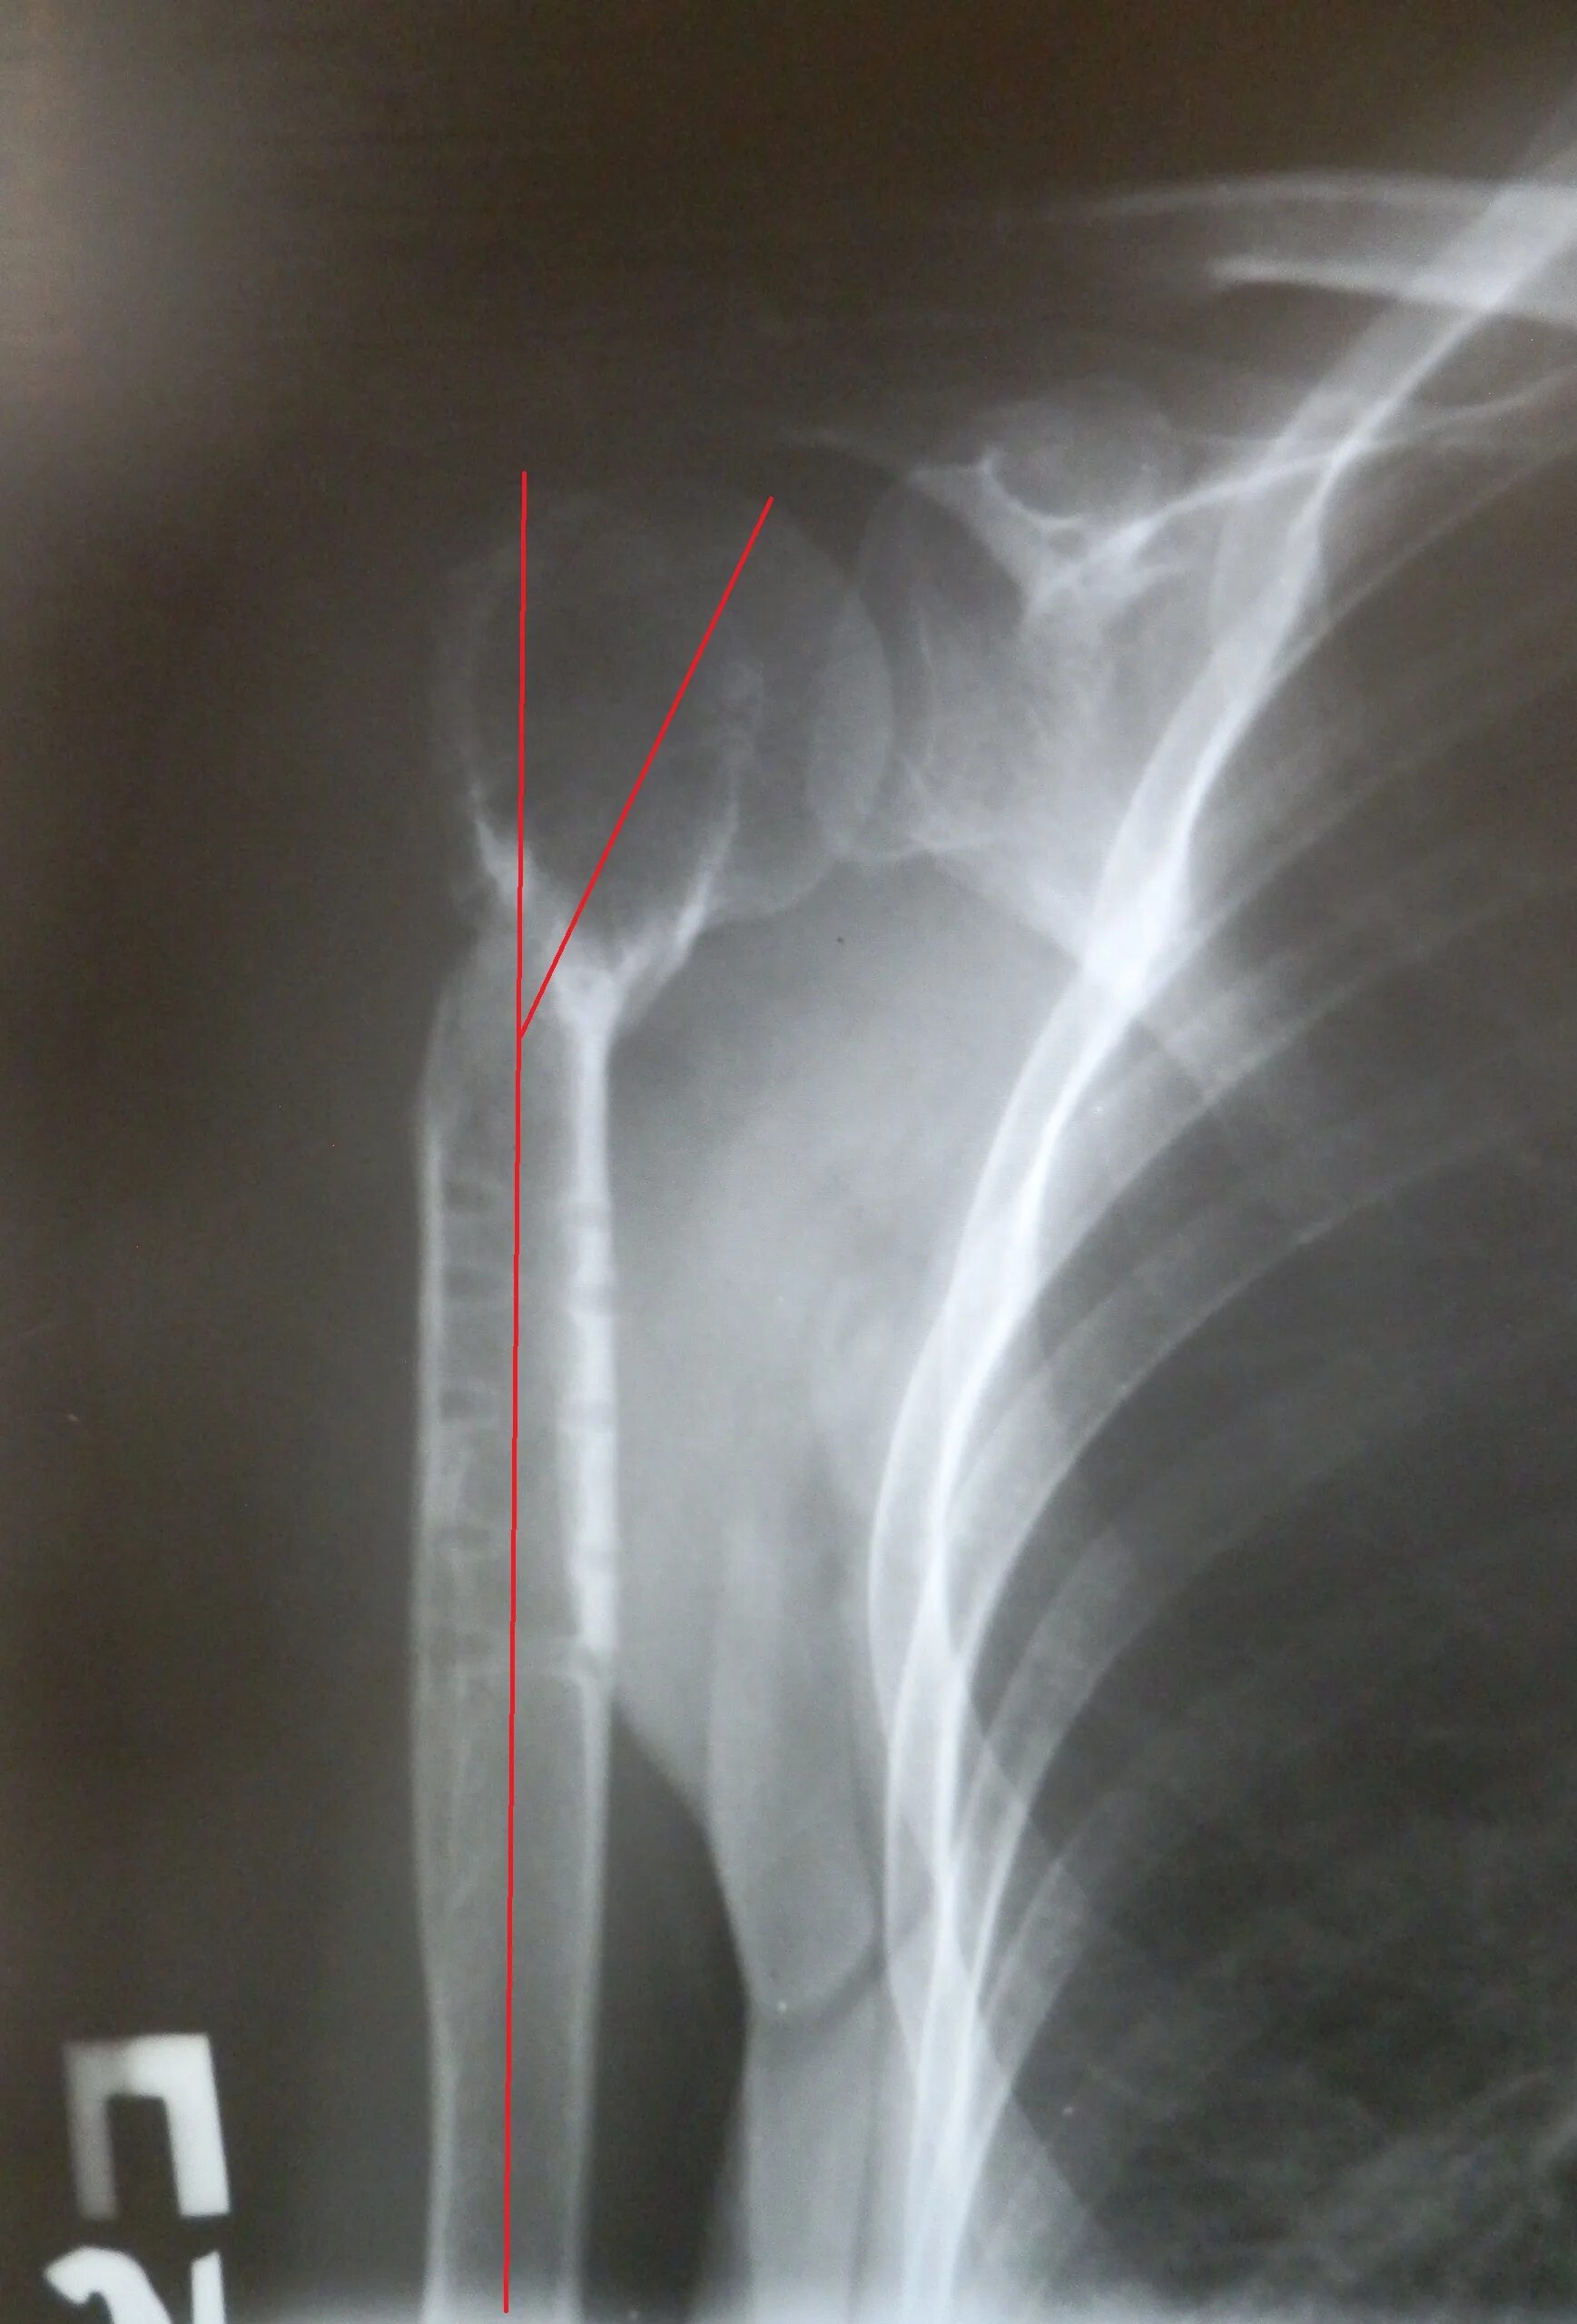

Сколько срастается плечевой перелом